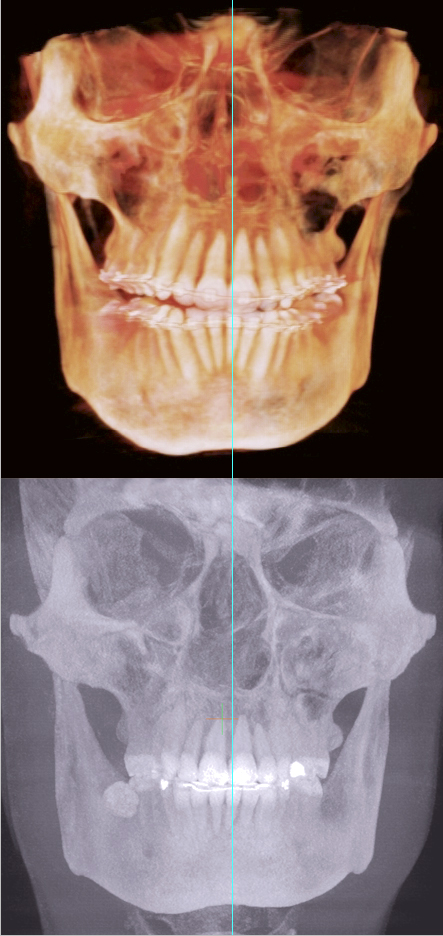

Your maxilla will come forward without surgery. As it comes forward, the bones around your condiles will rotate and your jaw will become loose and drop forward. Therefore, you will not be pulling JUST the maxilla forwards and end up looking like an inbred retard. Not only your maxilla will come forward but YOUR ENTIRE FACE WILL! Especially your cheekbones, so if you don't have cheekbones, you will get them with this technique. Your whole face will come forward and your jaw will follow along getting rid of TMJ forever! Below are my results...

|